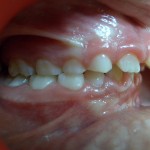

Photos avant et après traitement par Bielle

vue de droite